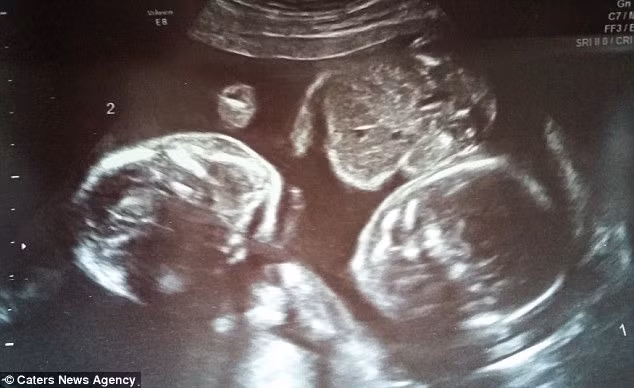

Thời gian đó, vợ chồng Hayley thường xuyên lui tới bệnh viện để theo dõi cái thai một cách sát sao. Như một điều kỳ diệu, hình ảnh siêu âm cho thấy 2 em bé ôm và nắm chặt tay nhau trong bụng mẹ. Tư thế ấy được duy trì cho đến khi Hayley được bác sĩ chỉ định mổ vào tuần thứ 34 vì không muốn tăng thêm nguy cơ cho 3 mẹ con. Ngay sau khi chào đời, 2 bé được đưa vào khu chăm sóc đặc biệt vì có dịch trong phổi và khó tự thở.